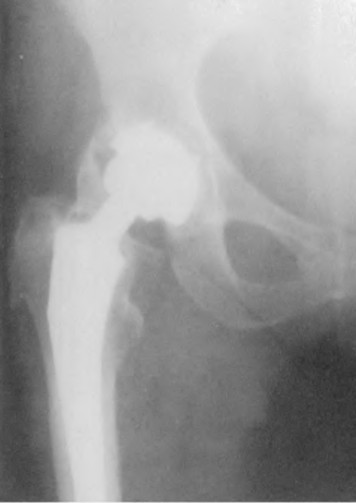

A 45-year-old female with developmental dysplasia of the hip (DDH) presents for THA. Preoperative radiographs show the femoral head is subluxated, with 80% proximal migration relative to the height of the normal true acetabulum. Based on the Crowe classification, what type of dysplasia does she have?